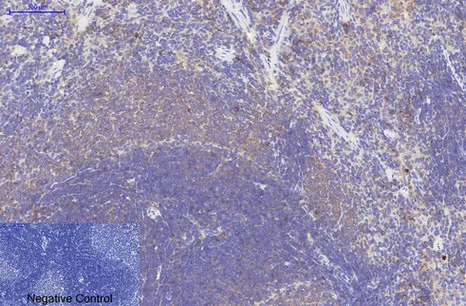

HER2(11H9)Mouse Monoclonal Antibody

Cat: AMM11986

Size1:50μL Price1:$118

Size2:100μL Price2:$220

Size3:200μL Price3:$380

Application:WB,IF-P,IF-F,ICC/IF,IHC-P

Reactivity:Human,Mouse,Rat

Conjugate:Unconjugated

Optional conjugates: Biotin, FITC (free of charge). See other 26 conjugates.

Gene Name:ERBB2